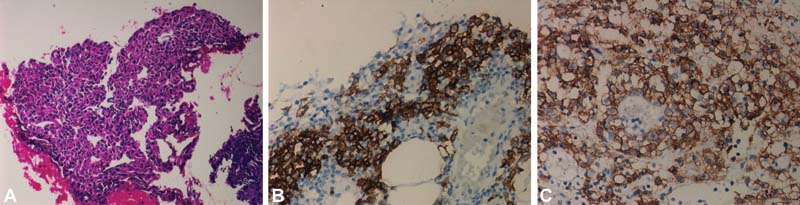

Histopathological findings of hematoxylin and eosin stain ([Fig. 2A]) showed sheets of large atypical lymphoid cells with plasmacytic differentiation with abundant cytoplasm, paranuclear hof, and large nuclei with an immunoblastic appearance. IHC was positive for CD38 ([Fig. 2B]), CD138 ([Fig. 2C]), and negative for LCA, CD79a, CD20, CD3, pancytokeratin, and calretinin. EBER in situ hybridization was not done. With this, diagnosis of relapsed PBL was established.

|?Fig. 2(A) Low power view showing sheets of plasmacytoid cells in omental fat. (B) Plasma cells showing strong membranous positivity with CD38. (C) Plasma cells showing strong membranous positivity with CD138.